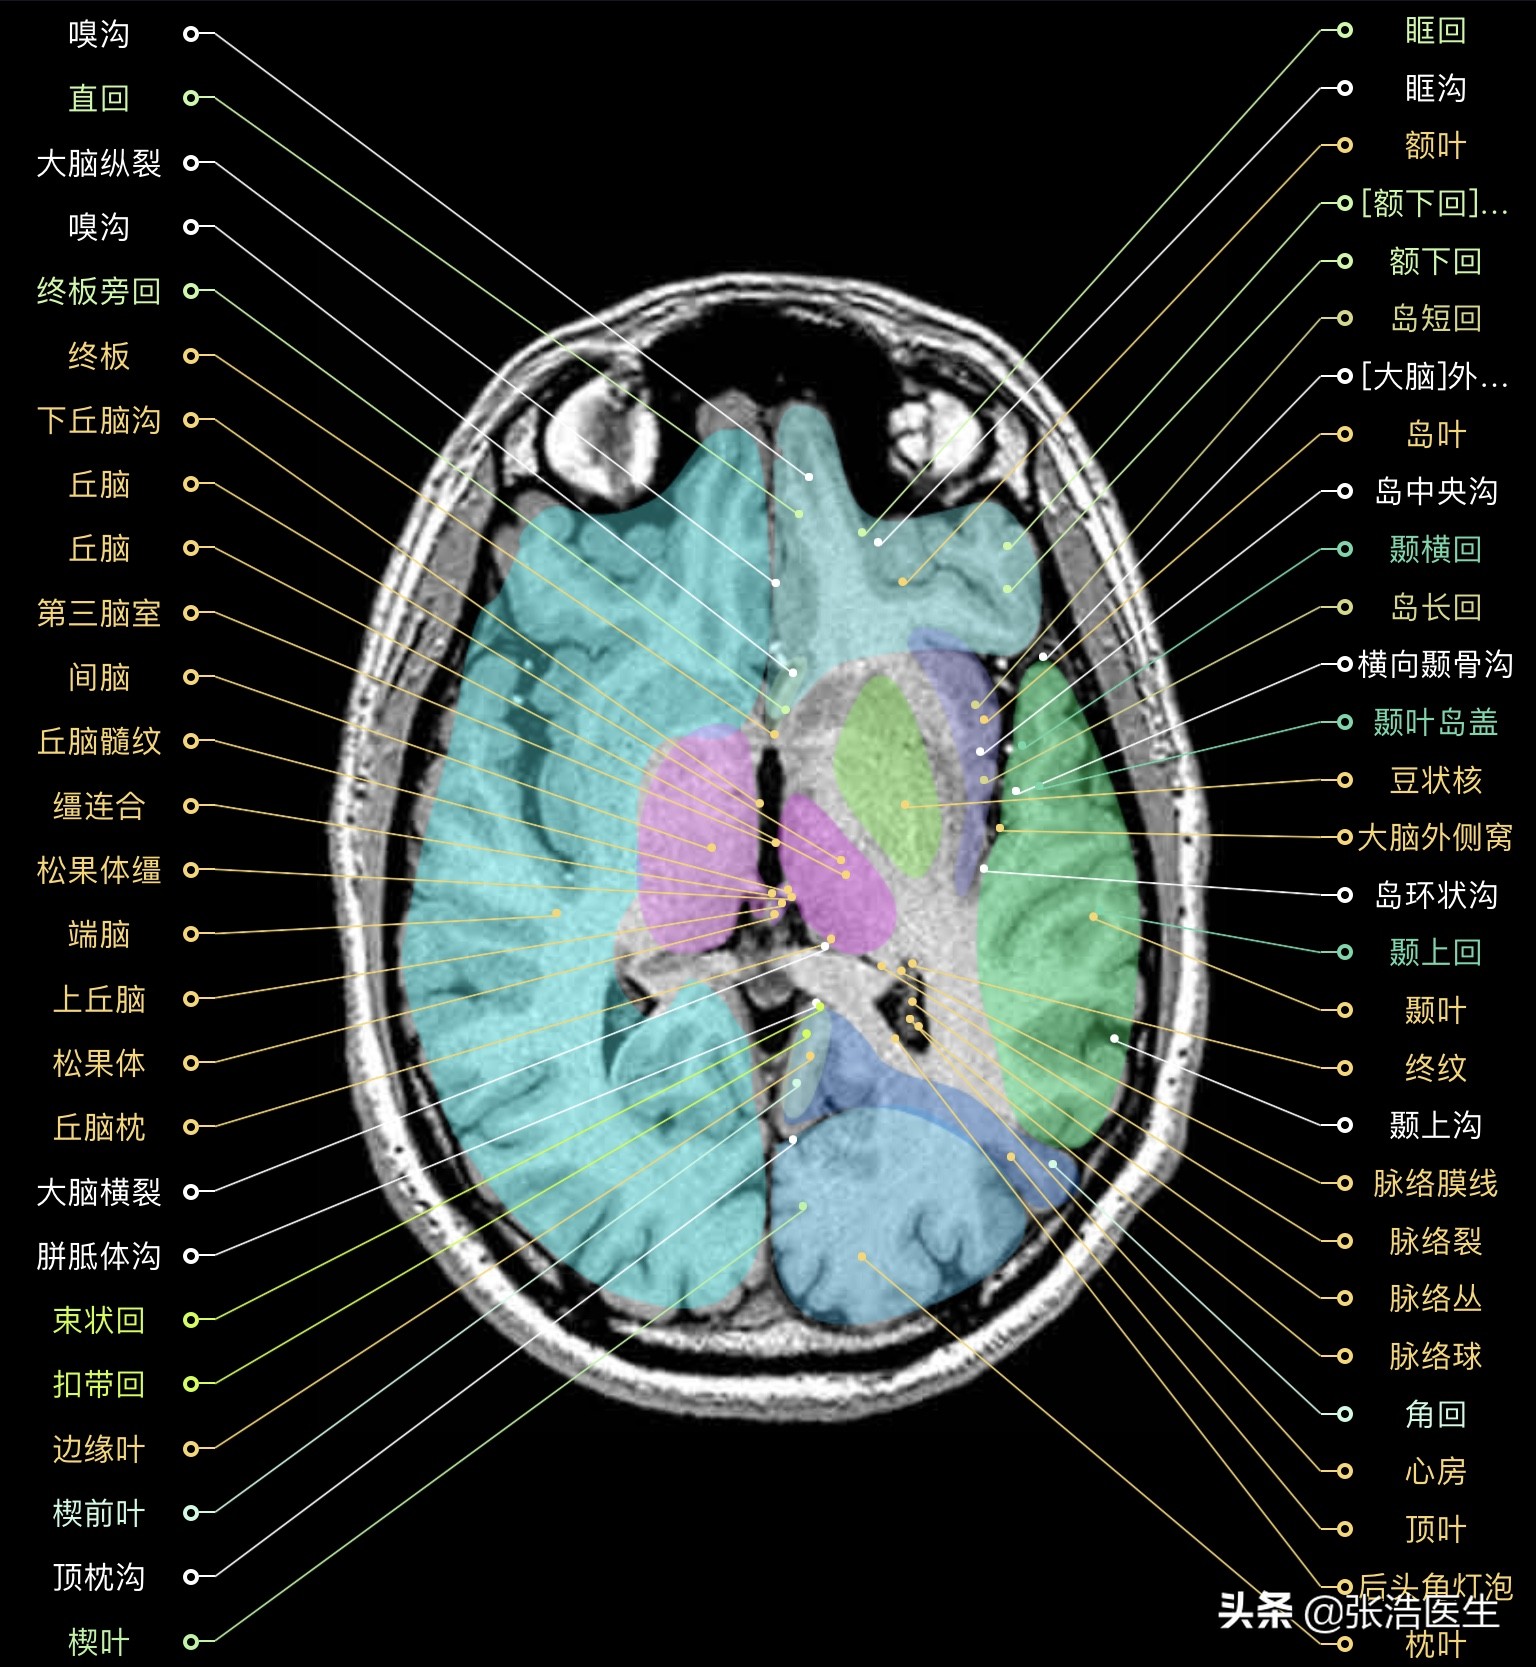

颅脑MRI横断面高清解剖图谱(图层4)